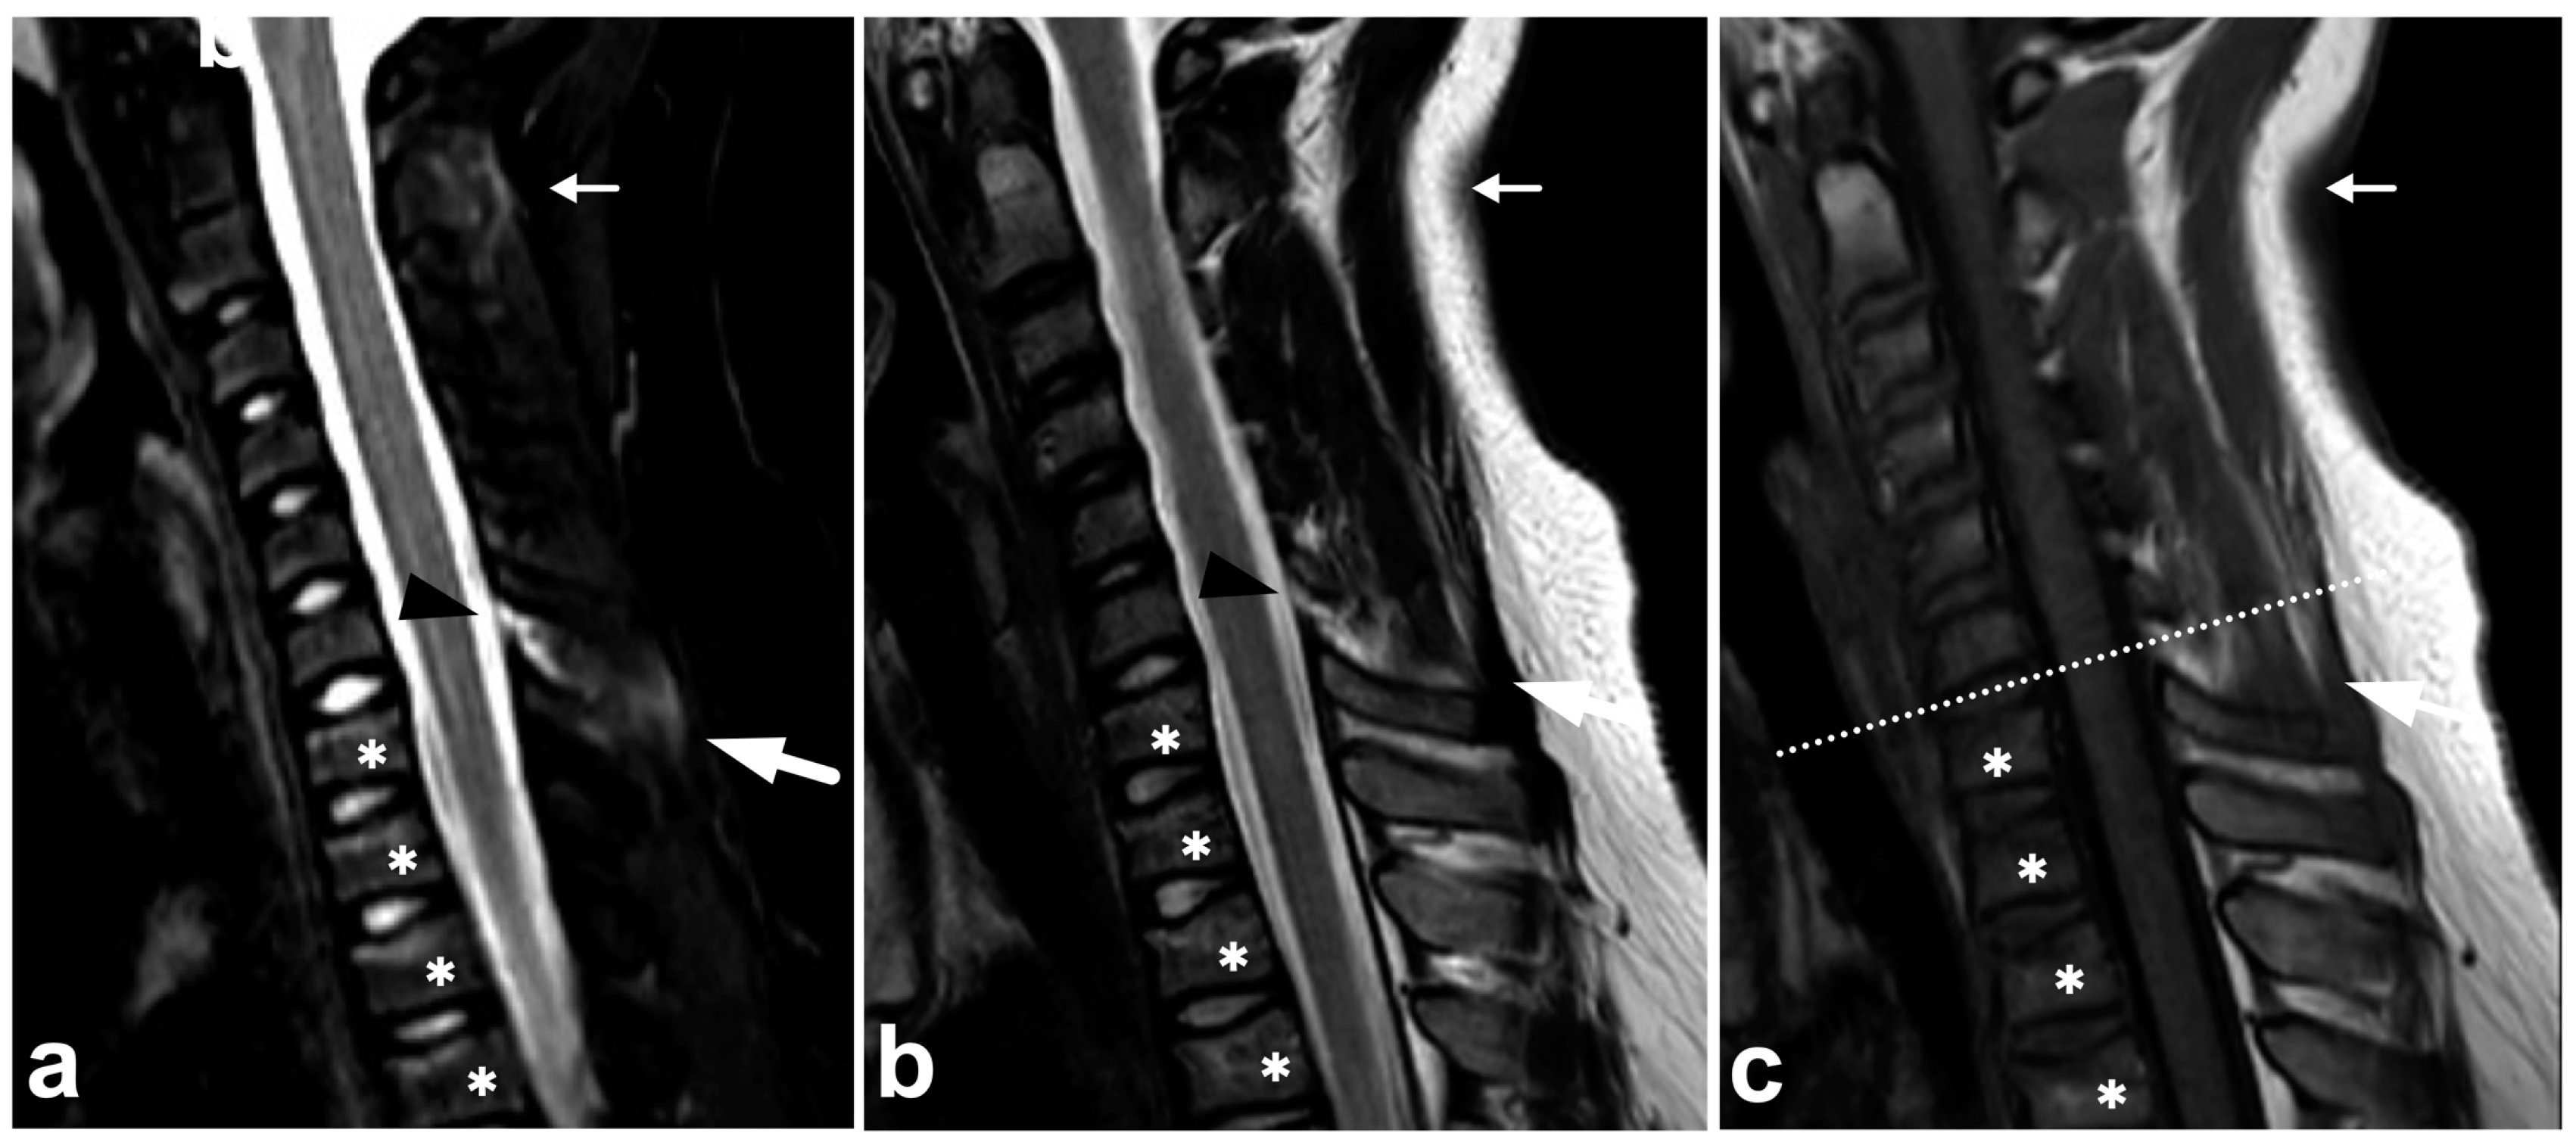

4.3. Anterior and Posterior Longitudinal Ligaments

Anterior and posterior longitudinal (ALL and PLL) injuries occur as part of a gross fracture–dislocation. The literature on the pediatric population’s isolated or non-dislocated ALL or PLL injuries is scarce. These injuries might be rare, especially in younger children [49], but the overall incidence is unknown. Moreover, in our clinical practice, we have found non-dislocated ALL and PLL injuries uncommon. An example of a discrete, partial ALL tear as a part of a non-dislocated flexion–extension cervical spine injury is presented in Figure 10.

Figure 10.

(a) Sagittal T2-weighted. (b) Sagittal STIR. (c) Sagittal STIR, cropped image. (d) Sagittal STIR, cropped right-sided off-midline image. A 17-year-old male, motor vehicle accident. Cervical spine injury at level C6/7 in particular. Compression fractures in the vertebral bodies C7, Th1, and Th3 (asterisks) and right-sided processus articular superior fracture in C7 (black arrowhead). ALL is partly torn at level C6/7 (white arrows), best seen in image (d). Moreover, the intervertebral disc at level C6/7 is edematous and inhomogeneous due to discal injury. Intact ALL is demonstrated at level C7/Th1 (white arrowhead). Soft tissue edema is seen at the prevertebral space, interspinous ligaments, deep posterior cervical muscles, the interspinous ligament, and inside and outside the facet joint (curved arrows). PLL and ligamentum flavum are intact, and no malalignment is seen.